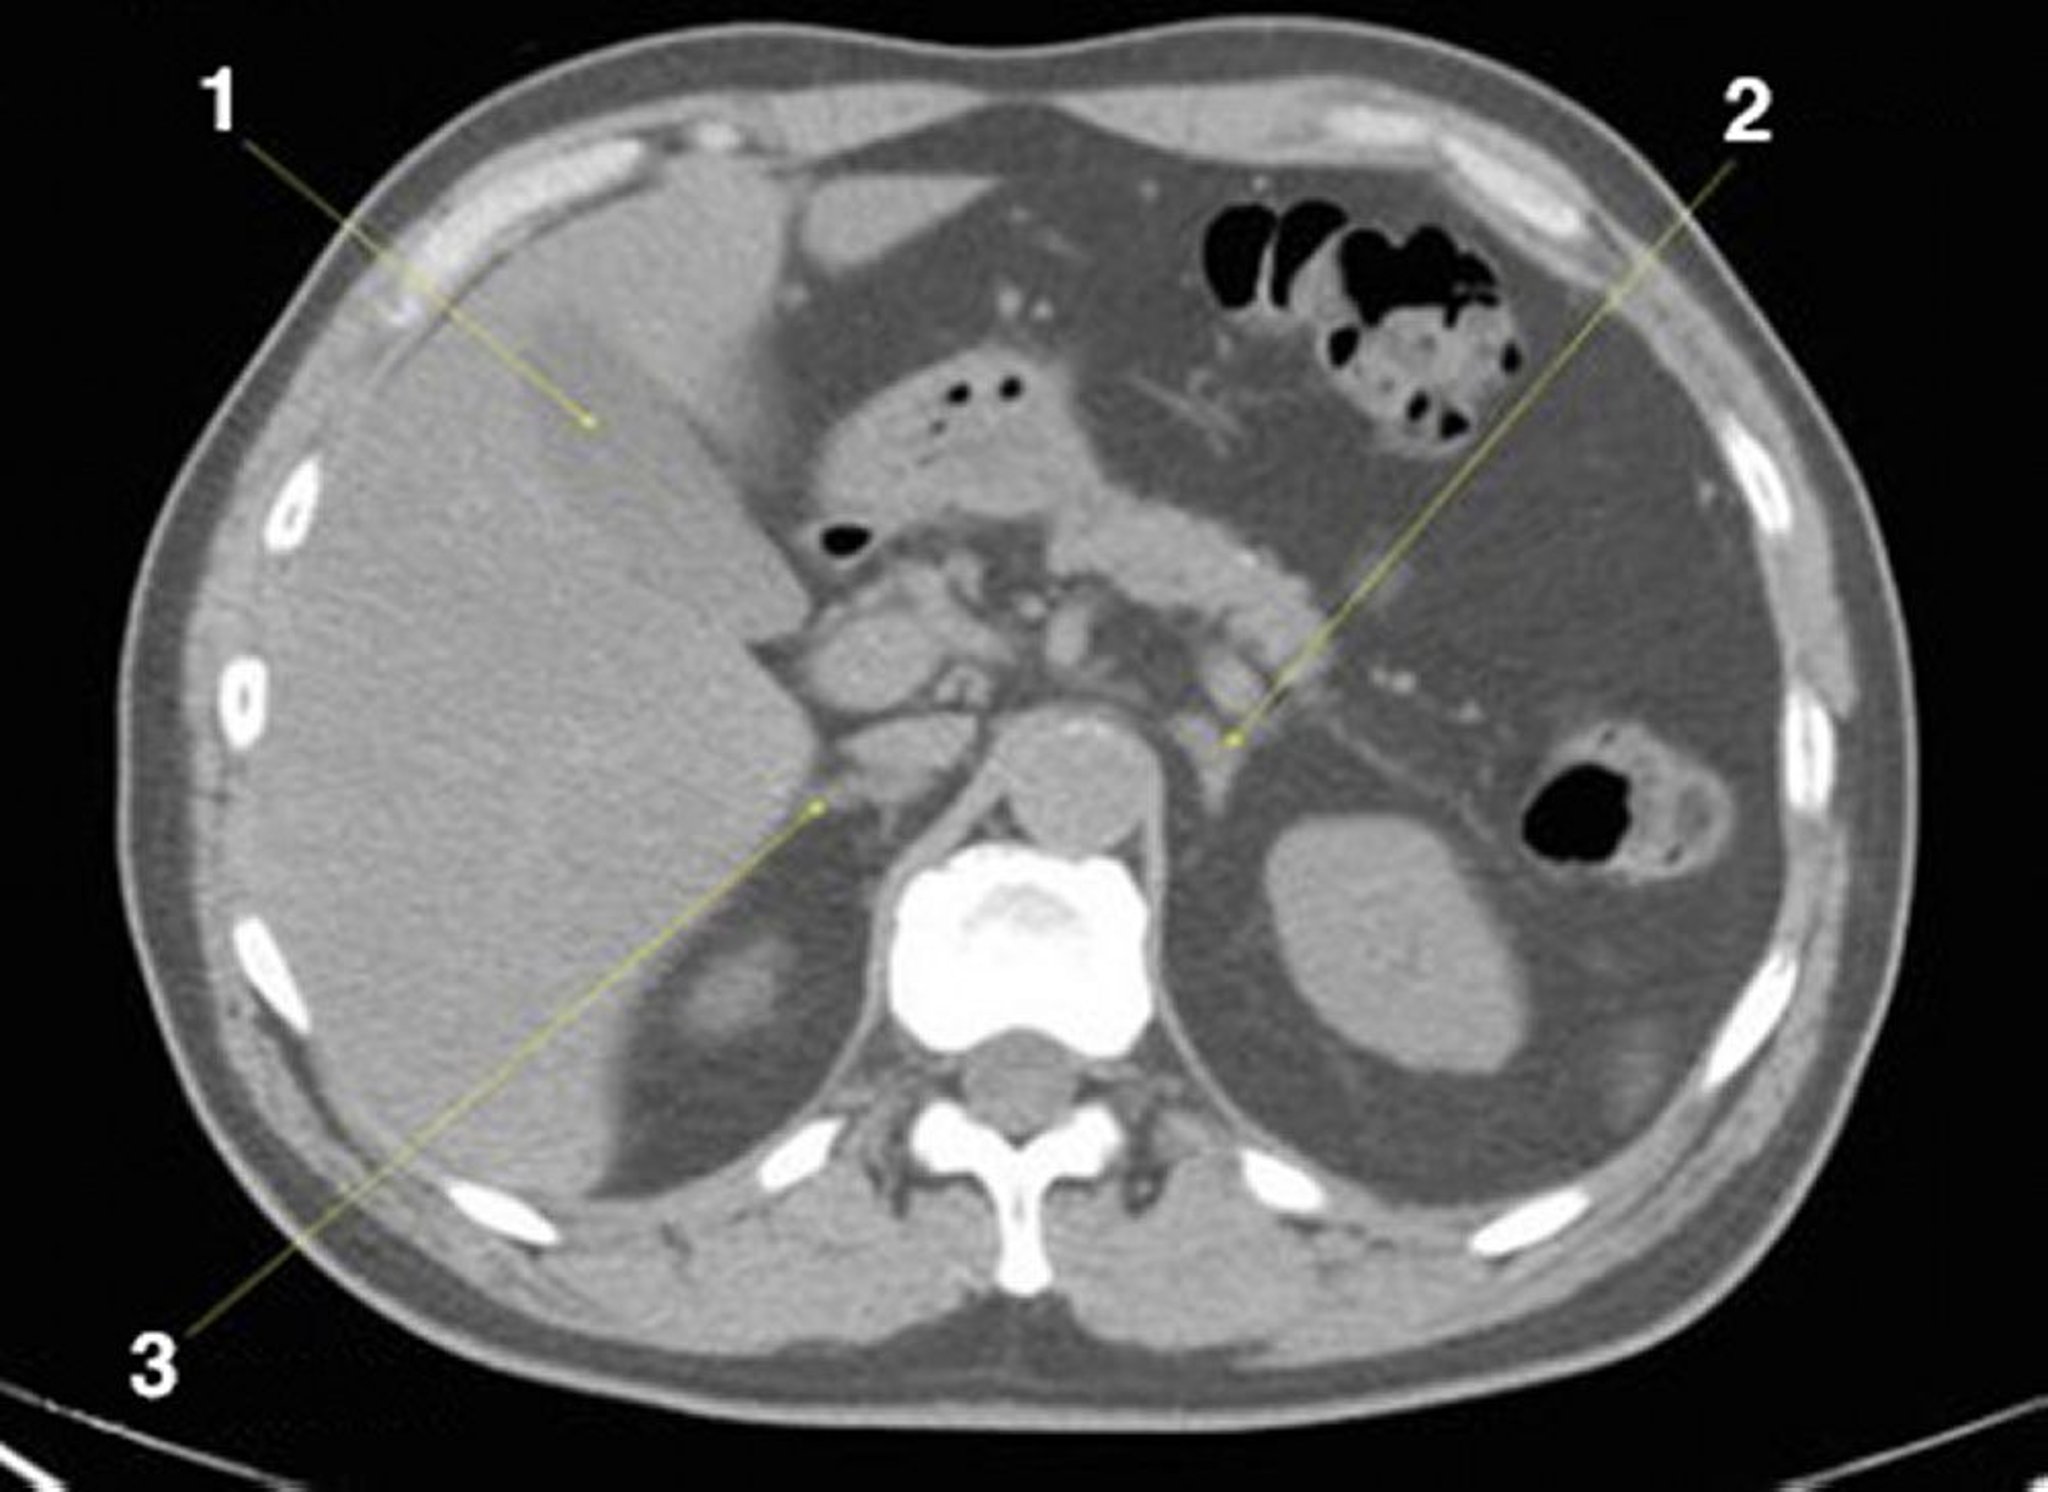

Noncontrast CT Scan of the Abdomen and Pelvis Showing Normal Anatomy (Slide 8)

1 = gallbladder; 2 = left adrenal gland; 3 = right adrenal gland.